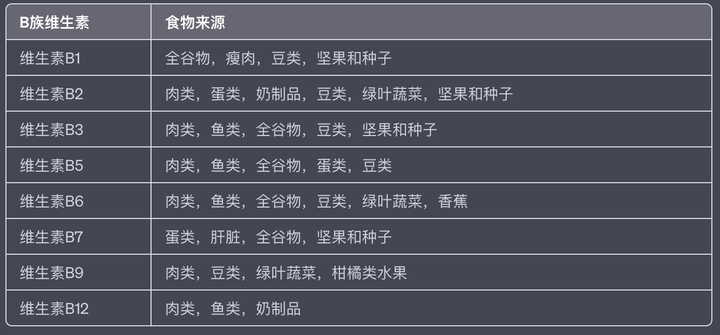

我推荐大家补VB,也就是维生素B族。

B族维生素是一个包含多个成员的大家庭,其中包括:维生素B1(硫胺),维生素B2(核黄素),维生素B3(烟酸),维生素B5(泛酸),维生素B6(吡哆醇),维生素B7(生物素),维生素B9(叶酸),维生素B12(钴胺)。

每种B族维生素都有其特定的作用,但它们在一起协同工作,帮助身体进行多种重要的生理过程。

它们都是我们身体不可或缺的一部分,尤其对于降低熬夜损伤来说,它们也在多方面发挥着作用。

比如保护神经系统,B族维生素,特别是B1、B6和B12,对神经系统健康至关重要。它们参与神经递质的合成,帮助神经系统正常运作,从而保护大脑免受熬夜带来的神经性疲劳和压力影响。

还可以促进新陈代谢,B族维生素在身体的能量代谢过程中扮演重要角色。它们帮助将食物转化为能量,使身体在熬夜时保持能量供应,从而减少疲劳感。

以及支持免疫功能,特别是维生素B6,是维持免疫系统健康的重要成分。它对免疫细胞的生成和活性有直接影响,帮助身体抵御疾病,从而降低熬夜可能增加的生病风险。

最后就是减少头油,降低肥胖。B族维生素可以帮助调节体内的脂肪代谢。特别是维生素B2和B6,它们可以帮助调节皮脂腺的功能,降低头皮油脂过多的问题。此外,由于B族维生素参与了糖和脂肪的代谢,可以帮助控制体重,从而降低由于熬夜导致的生活习惯不规律带来的肥胖风险。

如何来补充维生素B族呢?

补充维生素B族是一个很重要的事情,因为大部分B族维生素(如维生素B1、B2、B6、B9等)都不能在人体内自我合成或者存储,同时B族维生素是水溶性的。这意味着它们可以溶解在水中,不像脂溶性维生素(如维生素A、D、E和K)那样可以在体内储存。当我们摄入超过我们身体需要的水溶性维生素时,多余的部分会通过尿液排出体外。因此,我们需要每天通过饮食或者营养补充品的形式,每天都要摄入足够的B族维生素。

从饮食角度来说,需要从多种食物中获取维生素B族,但同时需要注意一点的是,因为B族维生素易溶于水,所以在烹饪过程中尽量避免长时间的煮炖或浸泡,以减少维生素的流失。